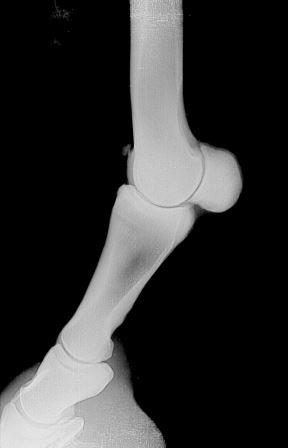

serv.it VET Vet-Check horse / radiological exam: fetlock Vet-Check horse / clinical exam: teeth control